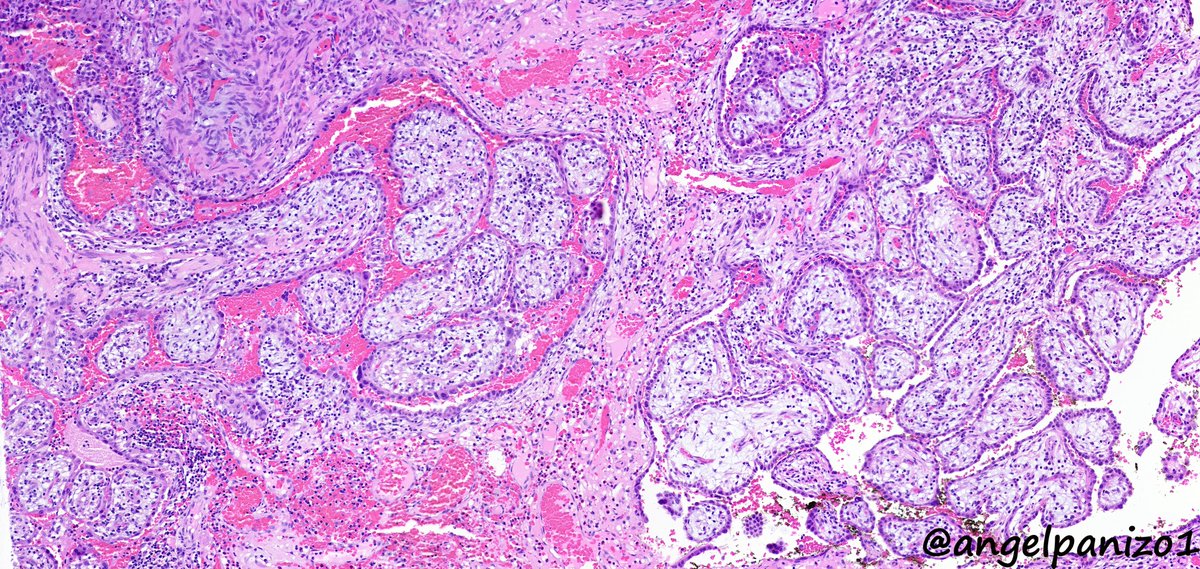

Incidental lung tumor... pulmonary hamartoma with unusual morphology?... what is your opinion? (2⃣) #PathTwitter #pulmpath @smlungpathguy @SansanoValero @yro854 @natasharekhtman @mkbaine @atman_ci @Path_Matt

angelpanizo1's tweet image. Incidental lung tumor... pulmonary hamartoma with unusual morphology?... what is your opinion? (2⃣) #PathTwitter  #pulmpath @smlungpathguy @SansanoValero @yro854 @natasharekhtman @mkbaine @atman_ci @Path_Matt